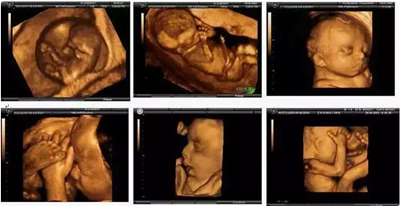

美国GE-E8四维数字彩超超越了传统超声的限制,较三维彩超更清晰真实,其出色的人体工程学设计能直观、立体的观察和显示人体器官的动态和三维结构。

四维彩超是录像,是动态的,可以让孕妈妈看到胎儿一连串的动作,三维彩超只能是某个时间点上的照片,四维彩超的就可以做成DV那样连续的,可以刻录U盘。因此,更多孕妈选择四维彩超检查。

准爸妈们通过四维彩超能够多方位、多角度观察宫内胎儿的生长发育情况。为早期诊断胎儿先天性体表畸形、先天性心脏疾病提供有效的科学依据,并可以直观的观测胎儿实时动态活动图像。

四维彩超检查